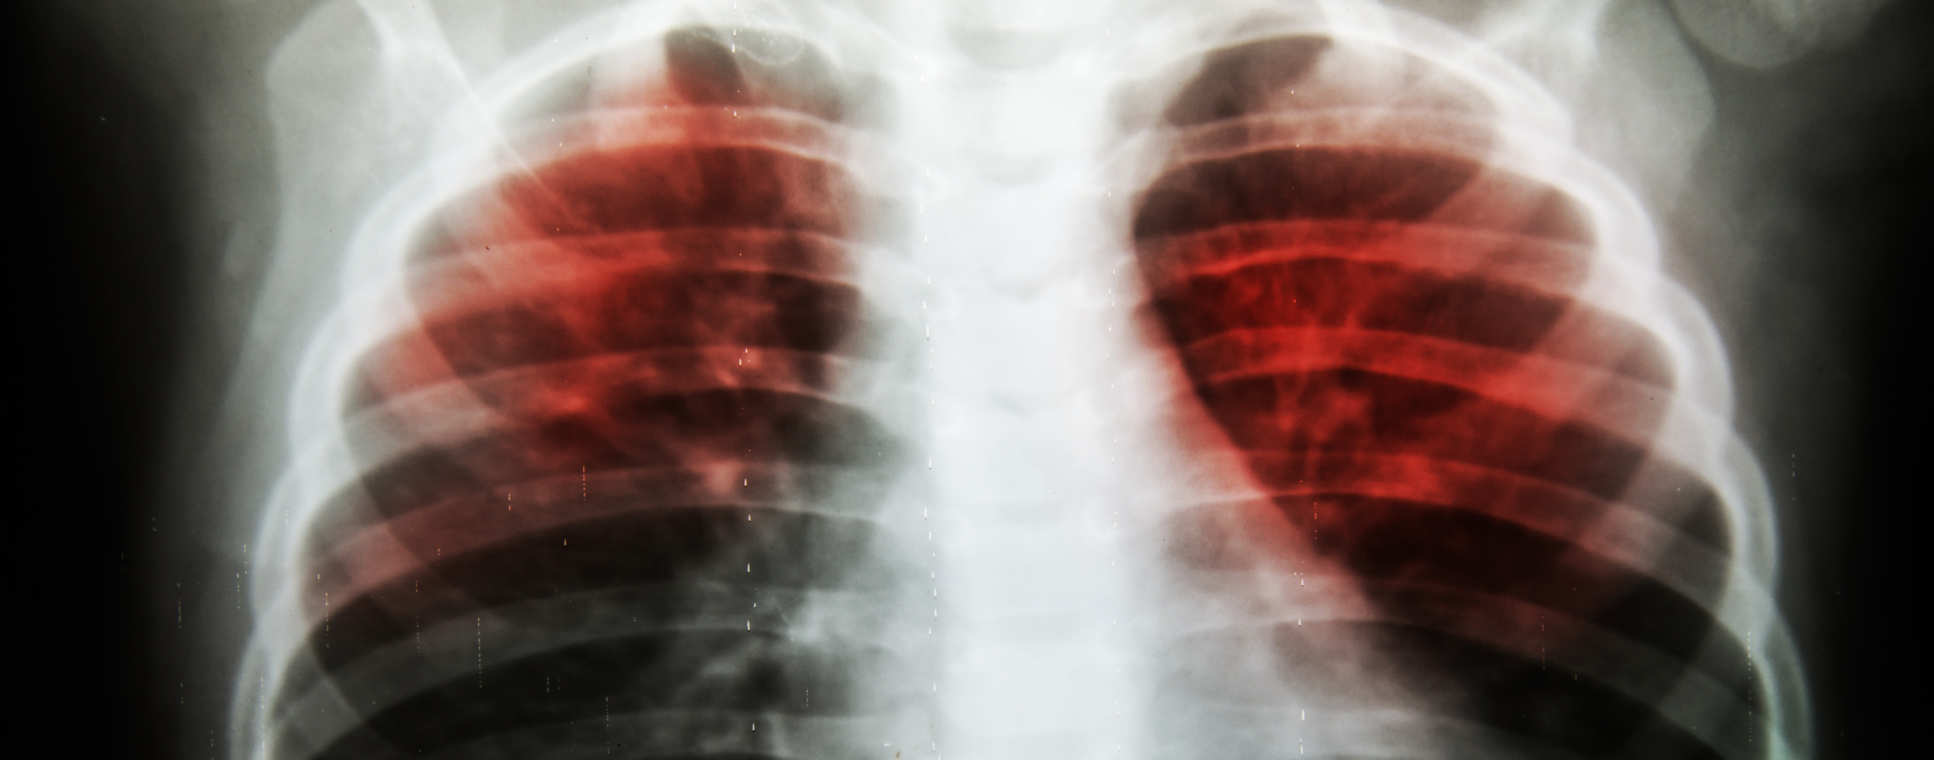

- Primary/secondary care interventions to improve screening, vaccination and treatment outcomes for infectious diseases such as tuberculosis (TB) in migrants

- The relationship between migration and TB, and the social, behavioural and psychological impact of TB and similar diseases of poverty on migrant and local populations